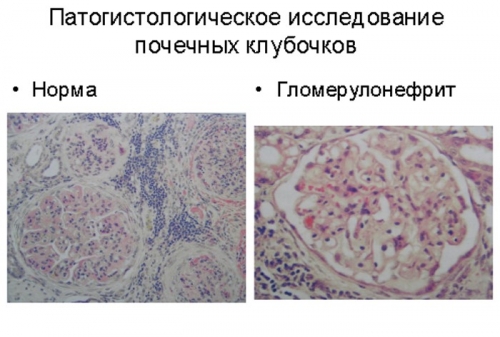

Механизм остро го диффузного гломерулонефрита